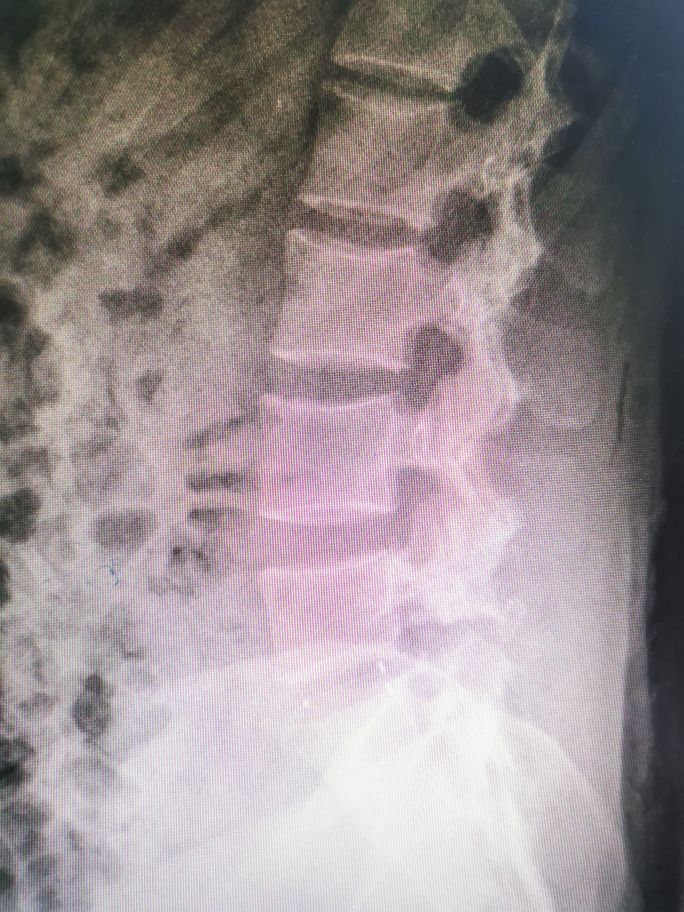

今天介绍这个病人有点特殊,主要是她太年轻了,才20岁,但她腰痛已经有两年了,近半年加重,影响生活所以来就诊。查体:腰部活动受限,下腰椎有压扣痛,双下肢感觉正常。x线及mr结果如下:

不知道大家看出什么问题没有,可能不是骨科专业的都不一定看得出来,好吧,跟大家解释一下:

磁共振上看到腰5的后缘相对于骶1的后缘前移了大概1/4椎体(正常应该对齐的),像这种上位椎体相对于下位椎体前移的就叫腰椎滑脱。腰椎滑脱按病因分类,具体可分为椎弓发育不良性、椎弓峡部裂性、退行性、外伤性、病理性和医源性导致的腰椎滑脱等。临床上以椎弓峡部裂性滑脱及退行性滑脱多见。腰椎滑脱的程度分级有多种,常用针对椎弓峡部裂性滑脱的Meyerding分级如下:

这样说比较抽象,其实最简单的办法就是把椎体分为四等份,超出1/4就是I度滑脱,超出2/4就是II度滑脱,依次类推。具体到这个病人,她上位椎体超出下位椎体1/4,那就是I度滑脱。那这个病人为什么会滑脱呢,也就是她属于何种类型的滑脱呢?首先她年纪很轻,不可能是退变性滑脱,大家看她的x线片: